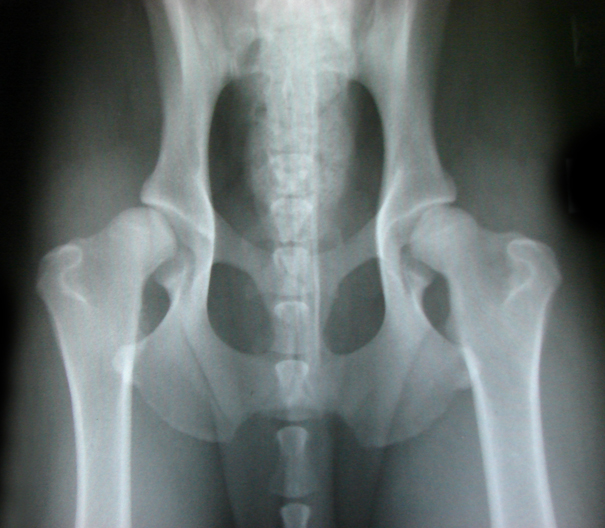

ДТБС у собак: рентгенограммы

Кликните на картинку для её масштабирования

Галерея изображений доступна только в электронном виде по следующему адресу::

ДТБС: степень "А" — норма

ДТБС: степень "B" — в пределах нормы

ДТБС: степень "С" — начальная форма

ДТБС: степень "D" — средняя форма

ДТБС: степень "E" — тяжёлая форма